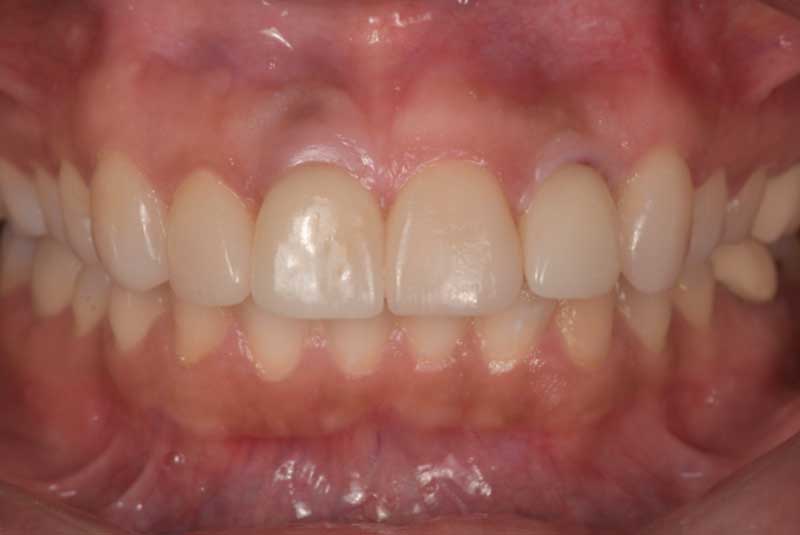

All on 6: Facial cut back (PFZ) Zirconia Full arch prosthesis for Maxilla and Mandible Before & After